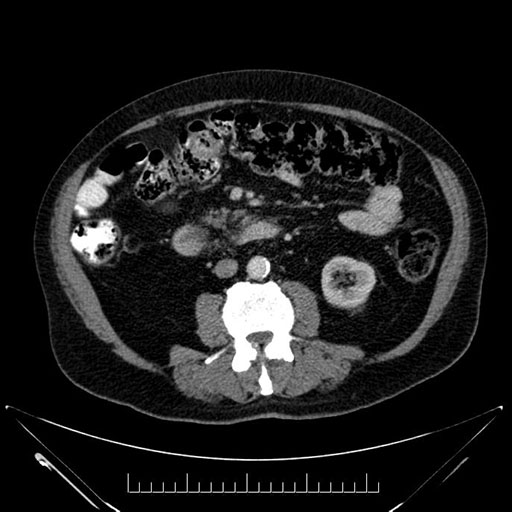

Axial - 3 months prior